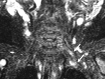

Fig 11.

A, An elongated C7 transverse process on the right (small arrow) and a cervical rib (long arrow) articulating with first thoracic rib on the left on a maximal-intensity-projection view of a neck CT of a patient presenting with cervical pain and bluish discoloration of both hands, more so on the left. MRA and MRV of the neck vessels (not shown) in abduction did not show any stenosis excluding vascular (arterial or venous) TOS. B–D, Sagittal CT (B) and sagittal MR imaging (C and D from lateral to medial) views in a neutral position on the left side demonstrate cervical rib−first rib articulation (star) and the cervical rib contacting the BPL fibers in the costoclavicular space, responsible for neurogenic TOS. The patient's symptoms on the right are due to the elongated C7 transverse process impinging the BPL within the interscalene triangle (not shown).